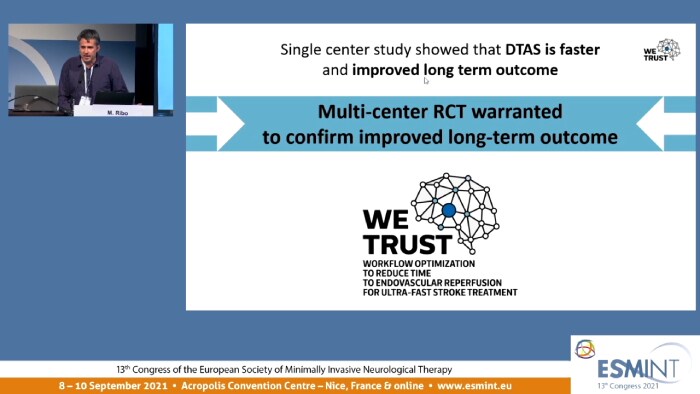

Dr. Marc Ribó explains how Direct to Angio Suite workflows shorten door to re-perfusion times for their ischemic stroke patients.

This symposium session took place during the ESMINT 2021.

‘If we think that the technology is ready to do that, I think we should go ahead and start taking our patients directly to the angio suite.’ Dr Marc Ribó (Hospital Val d’Hebron, Barcelona), PAIRS 2020 virtual event